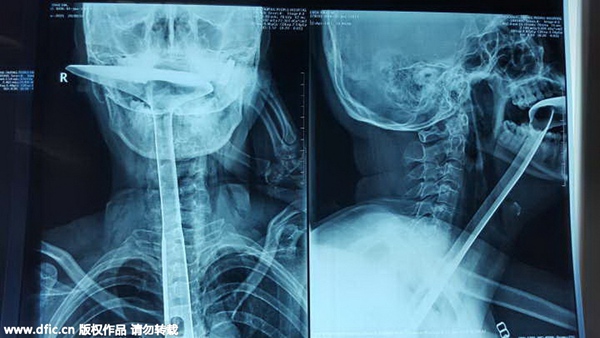

The X-ray picture shows a spetula stuck in the woman's throat. [Photo/IC]

Woman shoves spetula down her throat

A woman who shoved a 30-centimeter spetula down her throat stunned doctors with her extraordinary act in Humen county, Dongguan city, Guangdong province, reported South Metropolis Daily on Wednesday.

After her condition stabilized, she explained how it happened. She said she felt great difficulty breathing, with a lump in her throat when she was cooking. She remembered a local saying that using something to unblock her throat would work.

At first, she used her fingers but they were too short to unblock her throat. Then she chose chopsticks to stick into her throat. After breaking three chopsticks that way, she turned to a spetula and put the handle right into her throat. She soon felt it was impossible to breathe and that's when she went to the hospital for help.

The strange case made the doctors wonder if the woman was suffering from mental illness. But, surprisingly, she appeared to be perfectly sane. Doctors had to cut 20 centimeters out of 25 centimeters of her esophagus since it was badly damaged.

To enable her to eat, the doctors had to stretch her stomach up to her throat to connect with the rest of the esophagus.